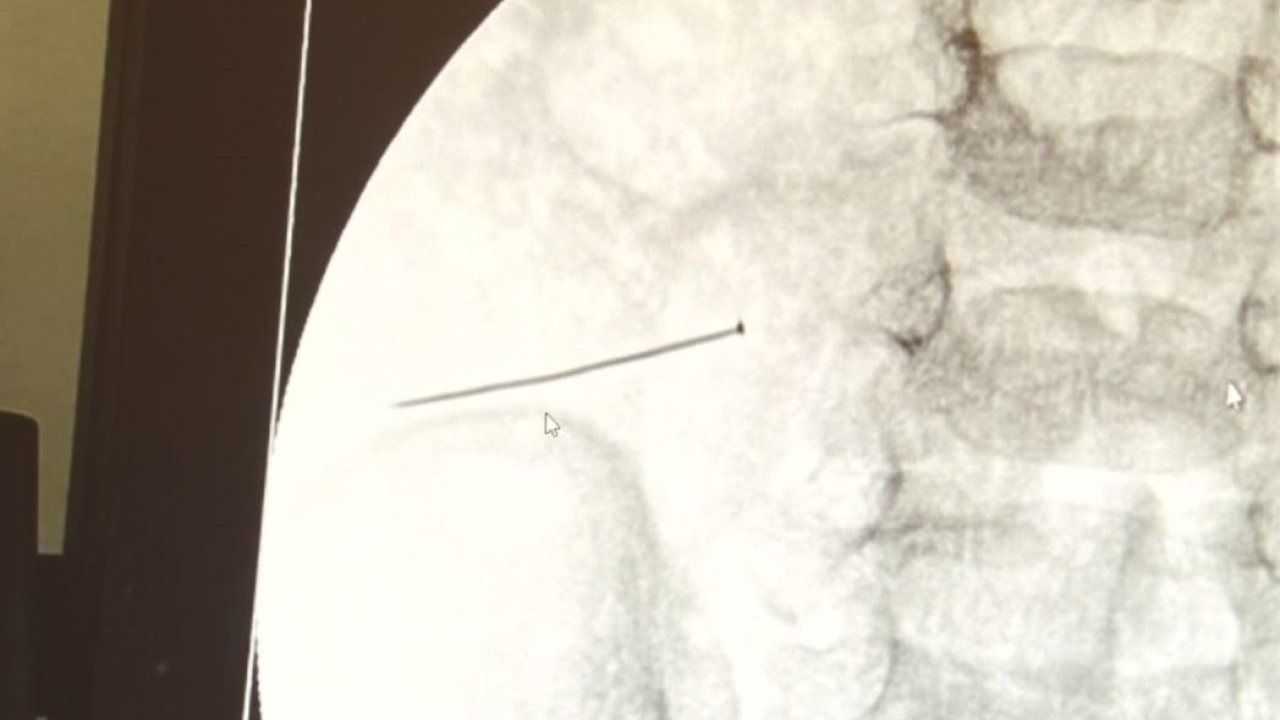

İstanbul’da 2 yaşındaki çocuk iddiaya göre toplu iğne yuttu sonrasında adeta karın ağrısıyla yerinde duramaz hale geldi. Babaanne, küçük çocuğun şikayetleri üzerine Şehit Prof. Dr. İlhan Varank Sancaktepe Eğitim ve Araştırma Hastanesi’ne götürdü. Burada yapılan tetkiklerde 2 yaşındaki çocuğun ince bağırsağında yaklaşık 3 santimlik toplu iğne olduğu ve bağırsağı deldiği belirlendi. Görüntülemeler sonrası 30 Ekim akşamı Çocuk Cerrahisi Kliniği Eğitim ve İdari Sorumlusu Doç. Dr. Sefa Sağ ve ekibi hemen ameliyata girdi. Başarılı operasyonla iğne olduğu noktadan alınırken aile de rahat bir nefes aldı. Doç. Dr. Sağ ise taburcu edilen hastasının durumuna ilişkin bilgi verirken yabancı cisim yutmalarına karşı ailelere önemli uyarılarda bulundu.

Çocuklarda yabancı cisim yutulmasına yönelik konuşan ve hastasına ilişkin bilgi veren Doç. Dr. Sefa Sağ, "Soluk borusuna kaçması durumunda çocuğun Allah göstermesin ölümüyle veya ömür boyunca yatağa bağımlı kalmasıyla neticelenebilecek sonuçlar doğurabiliyor. Yutulması durumunda da gastrointestinal sistemin herhangi bir yerine takılmadığı müddetçe ekseriyâ yabancı cisimlerin dışarıya çıkmasını bekliyoruz. Yabancı cisim yutulmasını 2 grupta inceleyebiliriz. Sıvı ve katı cisimler olarak sıvı; evde kullanılan kimyasal temizlik malzemelerinin yutulması çok ciddi problemler oluşturabilmekte. Ağızda, yemek borusunda ve midede yanıklar meydana getirebilmekte. Uzun dönemde çocukların hayat kalitesini oldukça etkileyen sonuçlar doğurabilmekte. Katı cisimlerden de ekseriyâ kendiliğinden çıkmasını bekleriz ancak böyle delici, kesici aletlerin yutulmasında ise herhangi bir bağırsağın veya gastrointestinal sistemin bir parçasında delinmeler meydana getirebiliyor. Bu çocuğumuzda da aynen böyle bir hadise meydana gelmişti. Sanırım 1 gün önce ailenin yuttuğunu tahmin ettiği bir yabancı cisim; toplu iğne. Ertesi gün bağırsakta delinmeyle sonuçlanmış ve çocukta da ciddi semptomlar meydana getirmişti. Bu şekilde hasta bize başvurdu. Tetkikler sonucunda yabancı cismi tespit ettik, semptomları ve bulgularına göre de çocuğu ameliyata aldık. Yaklaşık 3 santim boyunda bir toplu iğnenin ince bağırsağı deldiğini, ince bağırsaktaki içeriğin de karın içerisine dolduğunu gördük. Ameliyatı başarılı bir şekilde tamamladık, yaklaşık 1 saat süren bir ameliyattı" dedi.

Öte yandan, yaklaşık 3 santimlik toplu iğne filme yansıyan görüntüsüyle gözler önüne serildi.